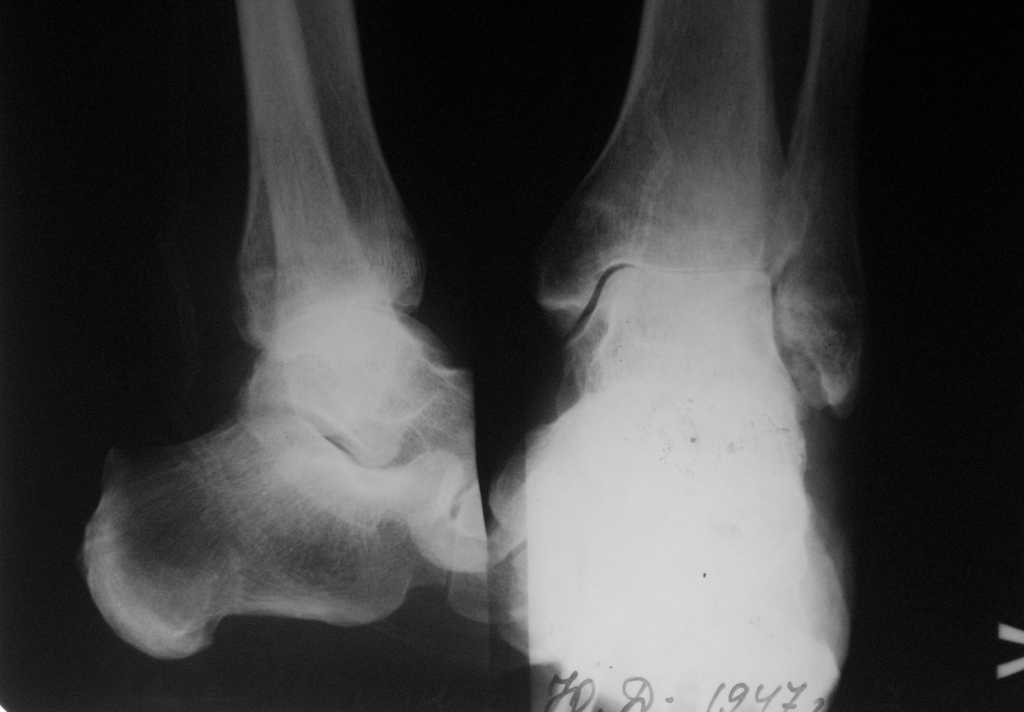

Пациент 57 лет, ранее выполнена пересадка сердца. Травма около 2-х лет назад. В настоящее время- передвигается при помощи костылей, выраженные боли и ограничение движений в голеностопном суставе. На конечность практически не наступает. Активный - рыбалка, охота, дача, дети и внуки.

Коллеги, просьба поучаствовать в обсуждении данного случая особенно тех, кто имел опыт эндопротезирования голеностопного сустава. Сам пациент настроен на протез, мы предлагаем артродез системой T2AAN Stryker.

Конечно, можно привести массу доводов за и против и артродеза, и эндопротеза. Хотя, очевидно, именно артродез надежнее обеспечит охоту, рыбалку и прочую дачу. Подтаранный сустав замыкать необходимости не видно.

А почему ничего не говорите о сосудах.... судя по снимкам на стопе кровоснабжение так себе. Раны то заживут при таком атеросклерозе?